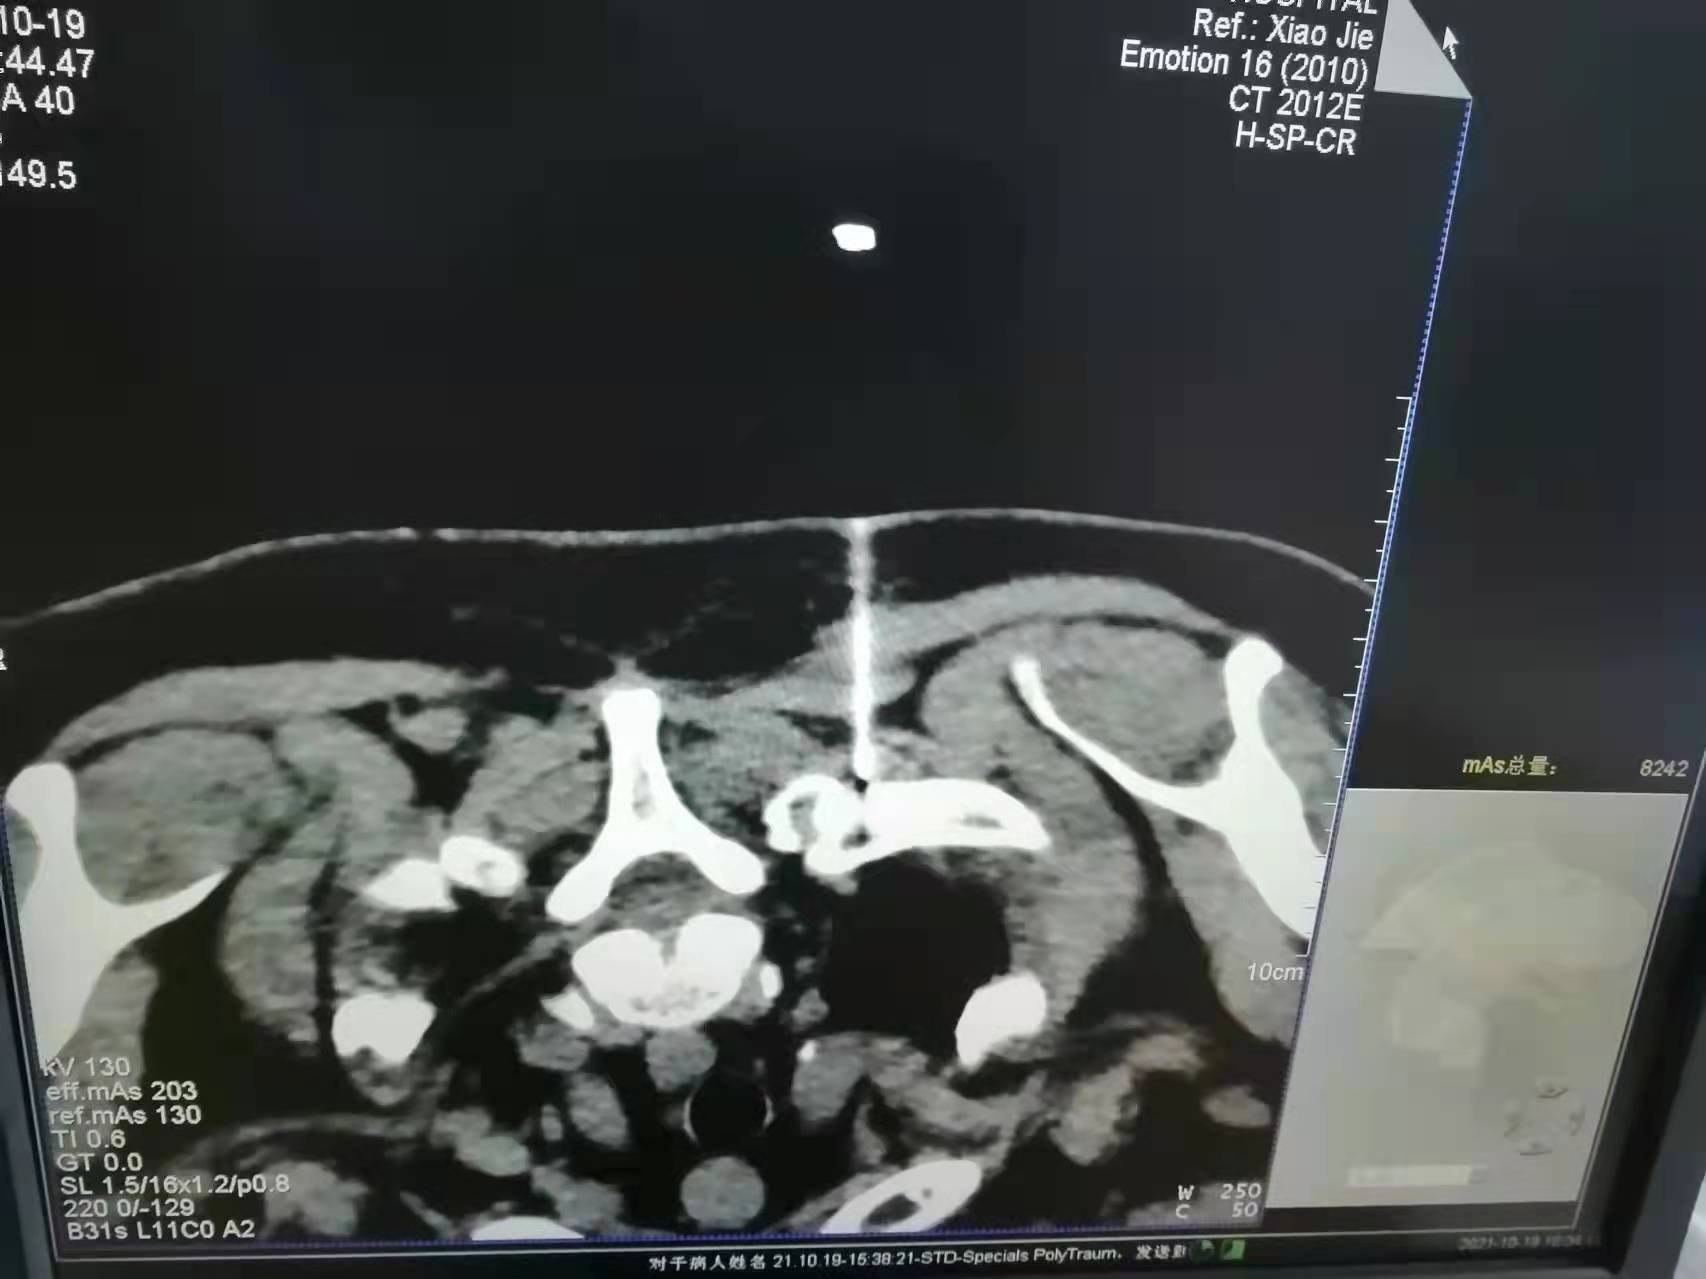

疼痛科相关技术展示 腰肌劳损是常见的腰痛原因,我院疼痛科通过CT引导脊神经后支阻滞治疗很好的解除了病人的疼痛和腰背肌肉的僵直状态。后续通过康复可达到患者满意的疗效。

腰椎间盘突出症的患者发病时往往痛不欲生,特别是急性发作期,我院疼痛科通过骶管治疗和CT引导下侧隐窝治疗缓解腰间盘压力,解除神经根水肿及炎性症状,为此类广大病友带来了福音。

骶管治疗和CT引导下的侧隐窝治疗有着不开刀、损伤小、疗效确切的优点!